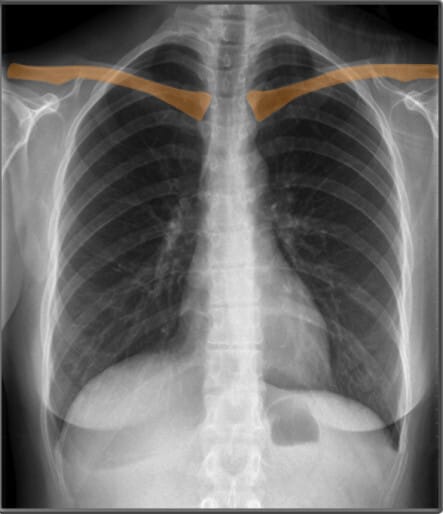

Bones (PA view)

흉부 X-ray에서는 쇄골(clavicle), 흉골(sternum), 견갑골(scapula), 척추(vertebral bodies) 등의 뼈 구조가 보이며, 정상적인 정렬을 확인하는 것이 중요합니다.

| 쇄골 (Clavicle) |

| ✅ 쇄골은 양측 상부에서 가로로 위치하며, 정상적으로 대칭적으로 보여야 합니다. 쇄골의 불균형은 환자의 자세 또는 외상으로 인한 손상을 의미할 수 있습니다. |

표시한 부분은 복장뼈의 가장 윗부분 두꺼운 뼈인 복장뼈자루 (Manubrium of Sternum)이라고 합니다.| 견갑골 (Scapula) |

| ✅ 어깨뼈라고도 불리며, 흉부 후방에서 삼각형 모양으로 나타납니다. 잘못된 촬영 자세에서는 폐야(lung field)를 가릴 수 있으므로 주의해야 합니다. |